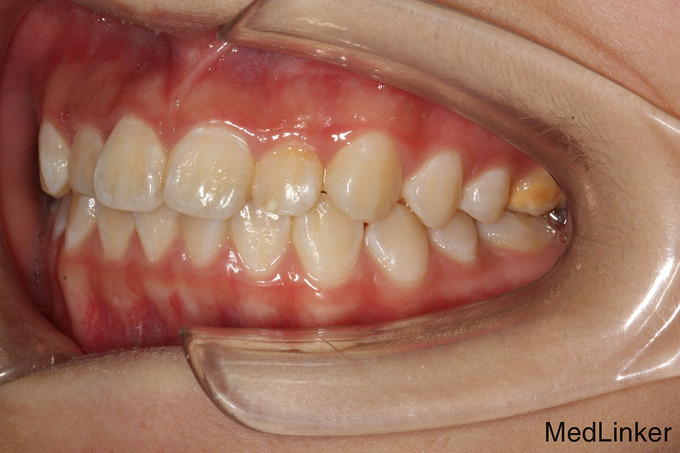

儿童牙齿矫正

12岁儿童,无过敏史,因牙列不齐,需要做正畸矫正术